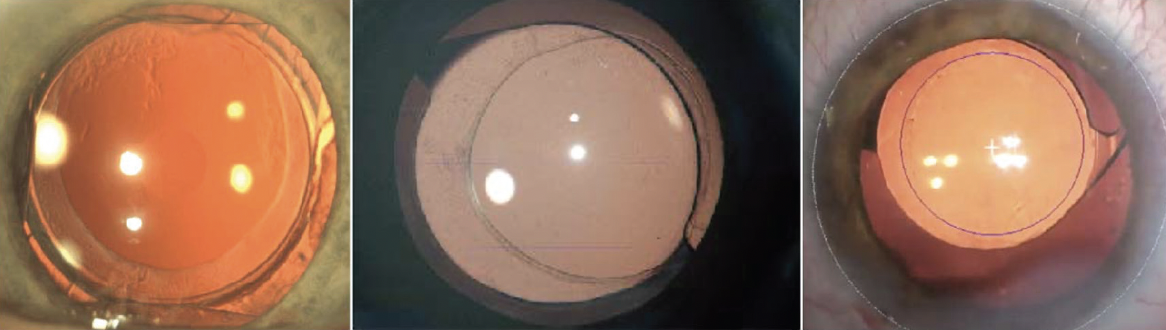

The ideal anterior capsulotomy is (Figure 1):

- circular and accurately sized between 4.8 and 5.5 mm;

- centered on the patient’s visual axis;1

- able to achieve 360º of symmetrical rim‐to‐optic coverage; and

- capable of producing a strong capsular edge.

Figure 1. An ideal capsulotomy is circular, with 360º of symmetrical rim-to-optic coverage, has a strong edge, and is centered on the visual axis.